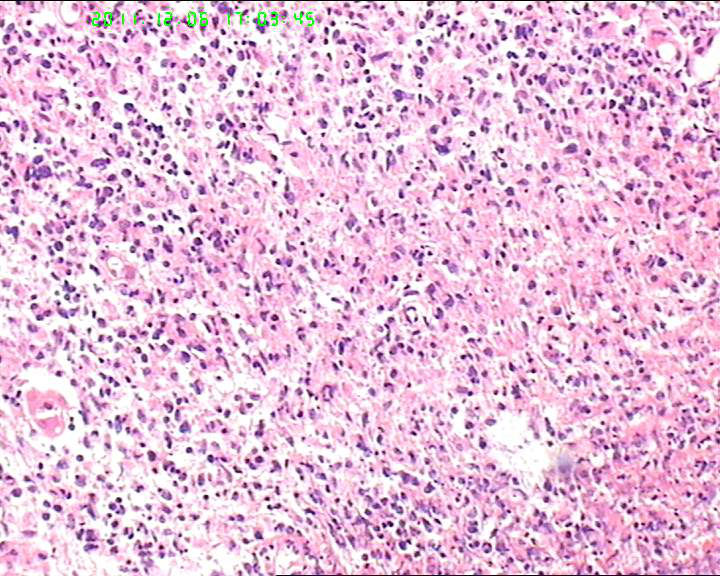

53岁女性患者,鼻腔肿物,中线恶网?韦格尔肉芽肿?

患者流脓涕1年,加重1月。左鼻腔息肉样增生物,质软,易出血。

送检灰白色绿豆大组织4块。

横纹肌肉瘤,恶黑,NK/T

组织内见大量形态各异的异型明显的细胞,弥漫分布,背景见肿瘤素质,首先考虑结外NK/T细胞淋巴瘤,鼻型;恶黑待排。